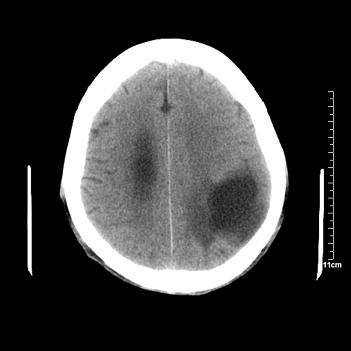

男性患者,72岁,近两天头晕来我院就诊。 因患者血压太高而未做增强,建议病人去市医院做mri检查。等得到mri随访结果再公布给大家。 测及左颞顶枕叶病灶ct值分别为5hu 30hu 729hu。

考虑左侧颞顶枕叶少突胶质细胞瘤。 今天随访患者手术病理结果 病理回报为胶质瘤2级 钙化

左侧颞顶枕叶大片状低密度影,呈均一水样密度,边界清楚,病灶边缘不规则片状钙化,左侧脑室后角扩大,中线结构未见移位,综合来看不像肿瘤,软化灶,钙化不好解释

左侧颞顶枕叶巨大囊性病灶,灶内见小片实性区且灶内及灶周围大量团块状钙化影,灶周水肿少.左侧室枕角内见环形钙化,可见较清晰前壁,钙化与室壁似有间隙.

囊变明显,钙化明显,部分实性组织,轻度占位,左侧脑室受压---考虑 少突胶质细胞瘤,畸胎瘤,寄生虫病

今天追踪患者家属手术病理结果 病理回报为胶质瘤2级并钙化

病理回报为胶质瘤2级并钙化